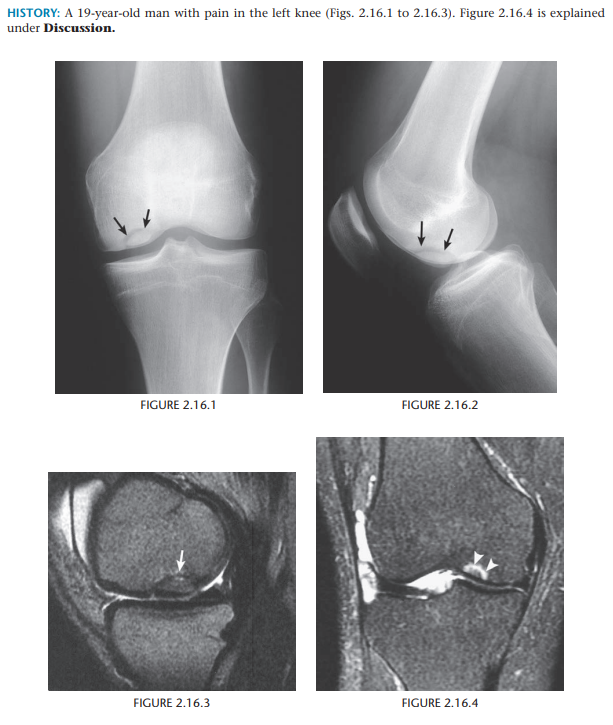

Osteochondritis dissecans (osteochondrosis) of the medial femoral condyle

An osteochondral fracture that was initially caused by shearing, rotatory, or

tangentially aligned impaction forces

semicircular lucency, with an adjacent bony fragment,

on the lateral aspect of the medial femoral condyle

(arrows)

Encircling fluid or focal cystic areas between the medullary canal and the fragment on MRI suggests a potentially loose or unstable fragment.